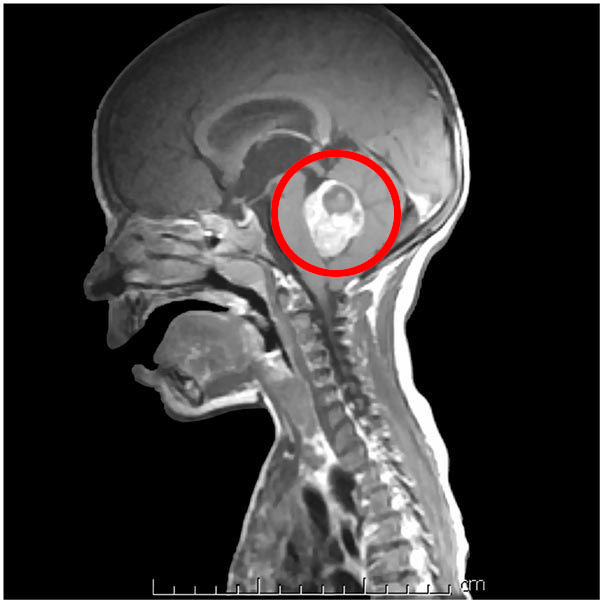

Medulloblastoma

- Descrizione: Tumore cerebrale Maligno. Provoca Cefalea, Vomito e perdita di equilibrio. Più comune nei bambini.